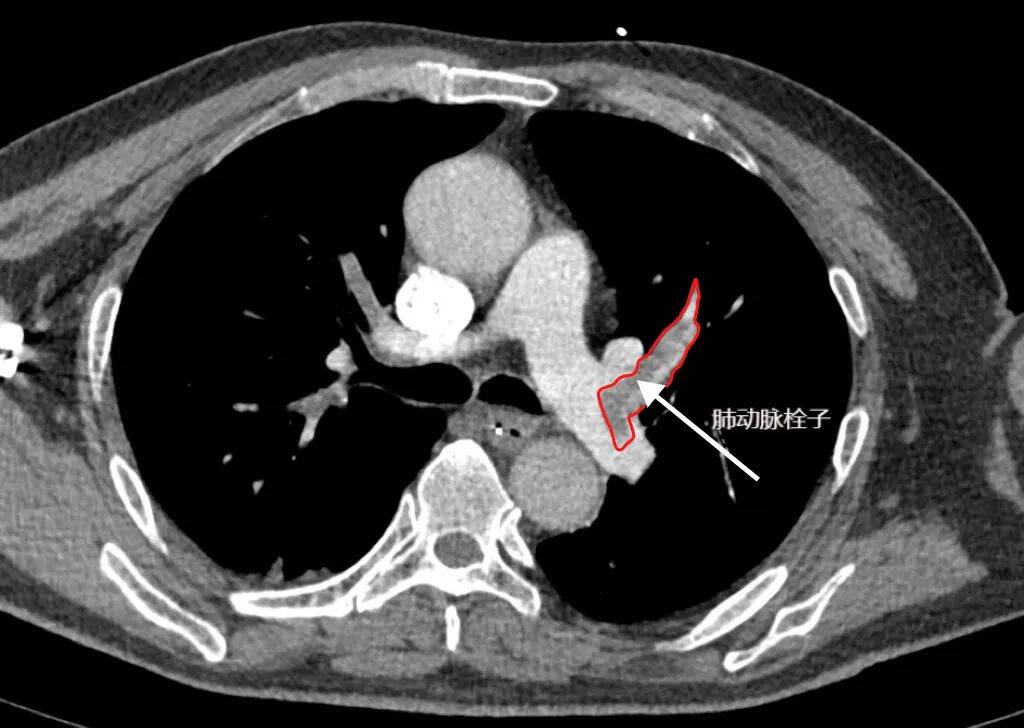

检查原理:通过肘静脉注射含碘造影剂,再用CT快速扫描肺部血管,让堵塞血管的血栓“显形”——影像上会看到肺动脉内有“充盈缺损”(就像水管里卡了一块石头,水流无法通过)。该检查速度快、准确率高,能清晰显示直径1-2毫米的小血栓,还能同时排查肺部感染、肿瘤等其他疾病,是目前各级医院诊断肺动脉栓塞的选择。

(上图CTPA为肺栓塞,可见黑色充盈缺损为肺动脉栓子堵塞了肺动脉血管通路(箭头处))